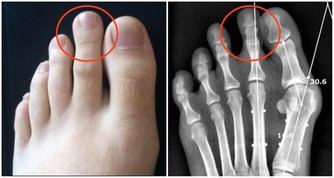

01.失眠、煩躁和腿抽筋